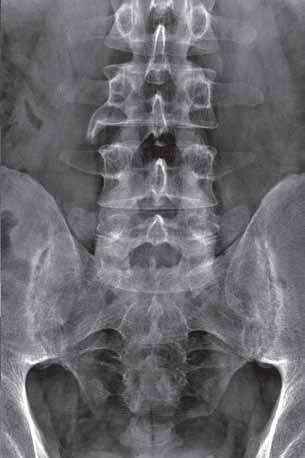

Zanik kostny (osteopenia, osteoporoza) występuje w przebiegu praktycznie wszystkich chorób reumatycznych (RZS, MIZS, innych chorób tkanki łącznej) oraz zapaleń infekcyjnych. Najwcześniej uwidacznia się przystawowo. Na radiogramach manifestuje się mniejszym wysyceniem przystawowych części kości. W miarę rozwoju choroby zanik kostny może przybierać charakter uogólniony. W badaniu RTG rąk zanik kostny ocenia się półilościowo na zasadzie pomiaru szerokości warstwy korowej trzonu 2 albo 3 kości śródręcza: suma szerokości warstw korowych od strony łokciowej i promieniowej w warunkach prawidłowych powinna być równa połowie szerokości trzonu na tym poziomie. Jeśli jest mniejsza, wskazuje to na zanik kostny. Przerostowy zanik kostny występuje w przewlekłym procesie zapalnym, charakteryzuje się rzadszym ułożeniem przerośniętych beleczek kostnych stanowiących główne linie architektoniki kości.

Najbardziej obiektywnym objawem zaniku kostnego jest ścieńczenie i rzadsze ułożenie beleczek istoty gąbczastej, a w okresie późniejszym również

ścieńczenie warstwy korowej. Trudności sprawia określenie nieznacznego stopnia zaniku kostnego; w takich przypadkach interpretacja powinna się zawsze opierać na radiogramach symetrycznych okolic anatomicznych.